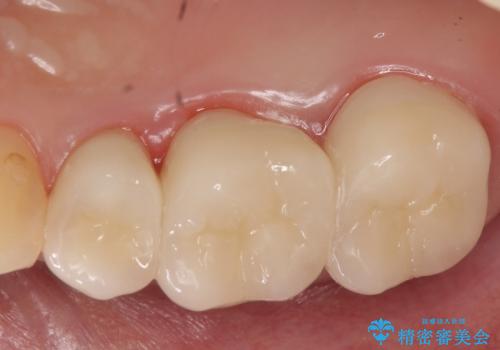

- 他院にて右上5番目の歯の根管治療を行っていたが、痛みが引かないため当院にいらっしゃった方の症例です。

右上5は再根管治療を行い症状の緩解を確認後、オールセラミッククラウンによる補綴を行いました。

右上6、7番目の歯もしみるとのことだったので古い樹脂及び虫歯を除去後、オールセラミッククラウンによる補綴を行いました。

※右上5は歯肉縁下まで虫歯だったため歯冠長延長術を提案しましたが、希望されませんでした。

今回用いたオールセラミッククラウンはジルコニアフレームという白い素材の上にセラミックを盛っているため、審美性が非常に高いのが特徴です。

また、ジルコニアは人工ダイヤモンドの材料にも使われているほど高い強度を持っており、そのためオールセラミッククラウンは審美性だけでなく、奥歯やブリッジの補綴も可能とするクラウンです。